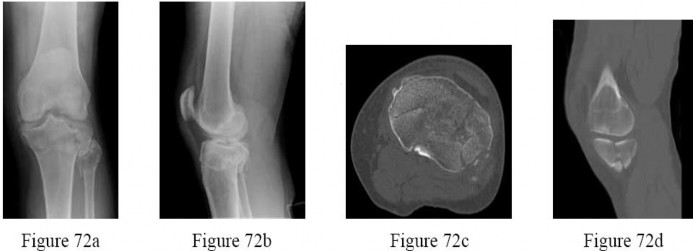

Question 13:

A 32-year-old woman complains of left knee pain. Radiographs show an eccentric, purely lytic lesion in the distal femoral epiphysis extending to the subchondral bone, without a sclerotic margin. Biopsy reveals multinucleated giant cells interspersed among mononuclear stromal cells. For recurrent or surgically unsalvageable cases of this specific tumor, which of the following is the most appropriate targeted medical therapy?

This is a Giant Cell Tumor (GCT) of bone. The neoplastic cells in GCT are actually the mononuclear stromal cells, which heavily express RANKL (Receptor Activator of Nuclear factor Kappa-B Ligand). This expression recruits and activates normal osteoclasts (the giant cells), causing massive osteolysis. Denosumab, a monoclonal antibody against RANKL, is the medical treatment of choice for unresectable or highly recurrent GCTs.